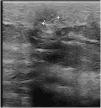

Quistes foliculares pigmentados múltiples. Imagen ecográfica

Multiple pigmented follicular cysts. Ultrasound imaging